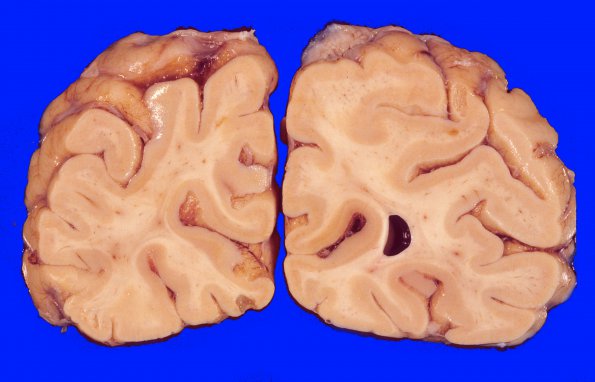

8A1  Arteriolosclerosis, Infarct, Old, pyramid & olive (Case 8) Occipital

Small white and gray matter infarcts are noted in this occipital lobe section.